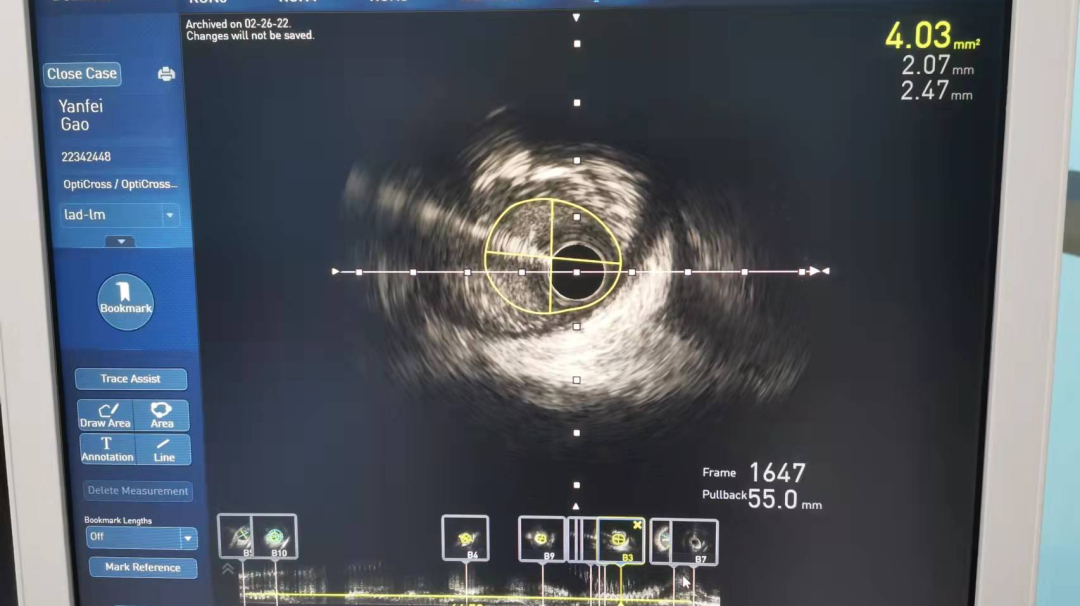

冠脉支架术前病变近端管腔面积4.03mm2

冠脉支架术前病变远端管腔面积2.23mm2